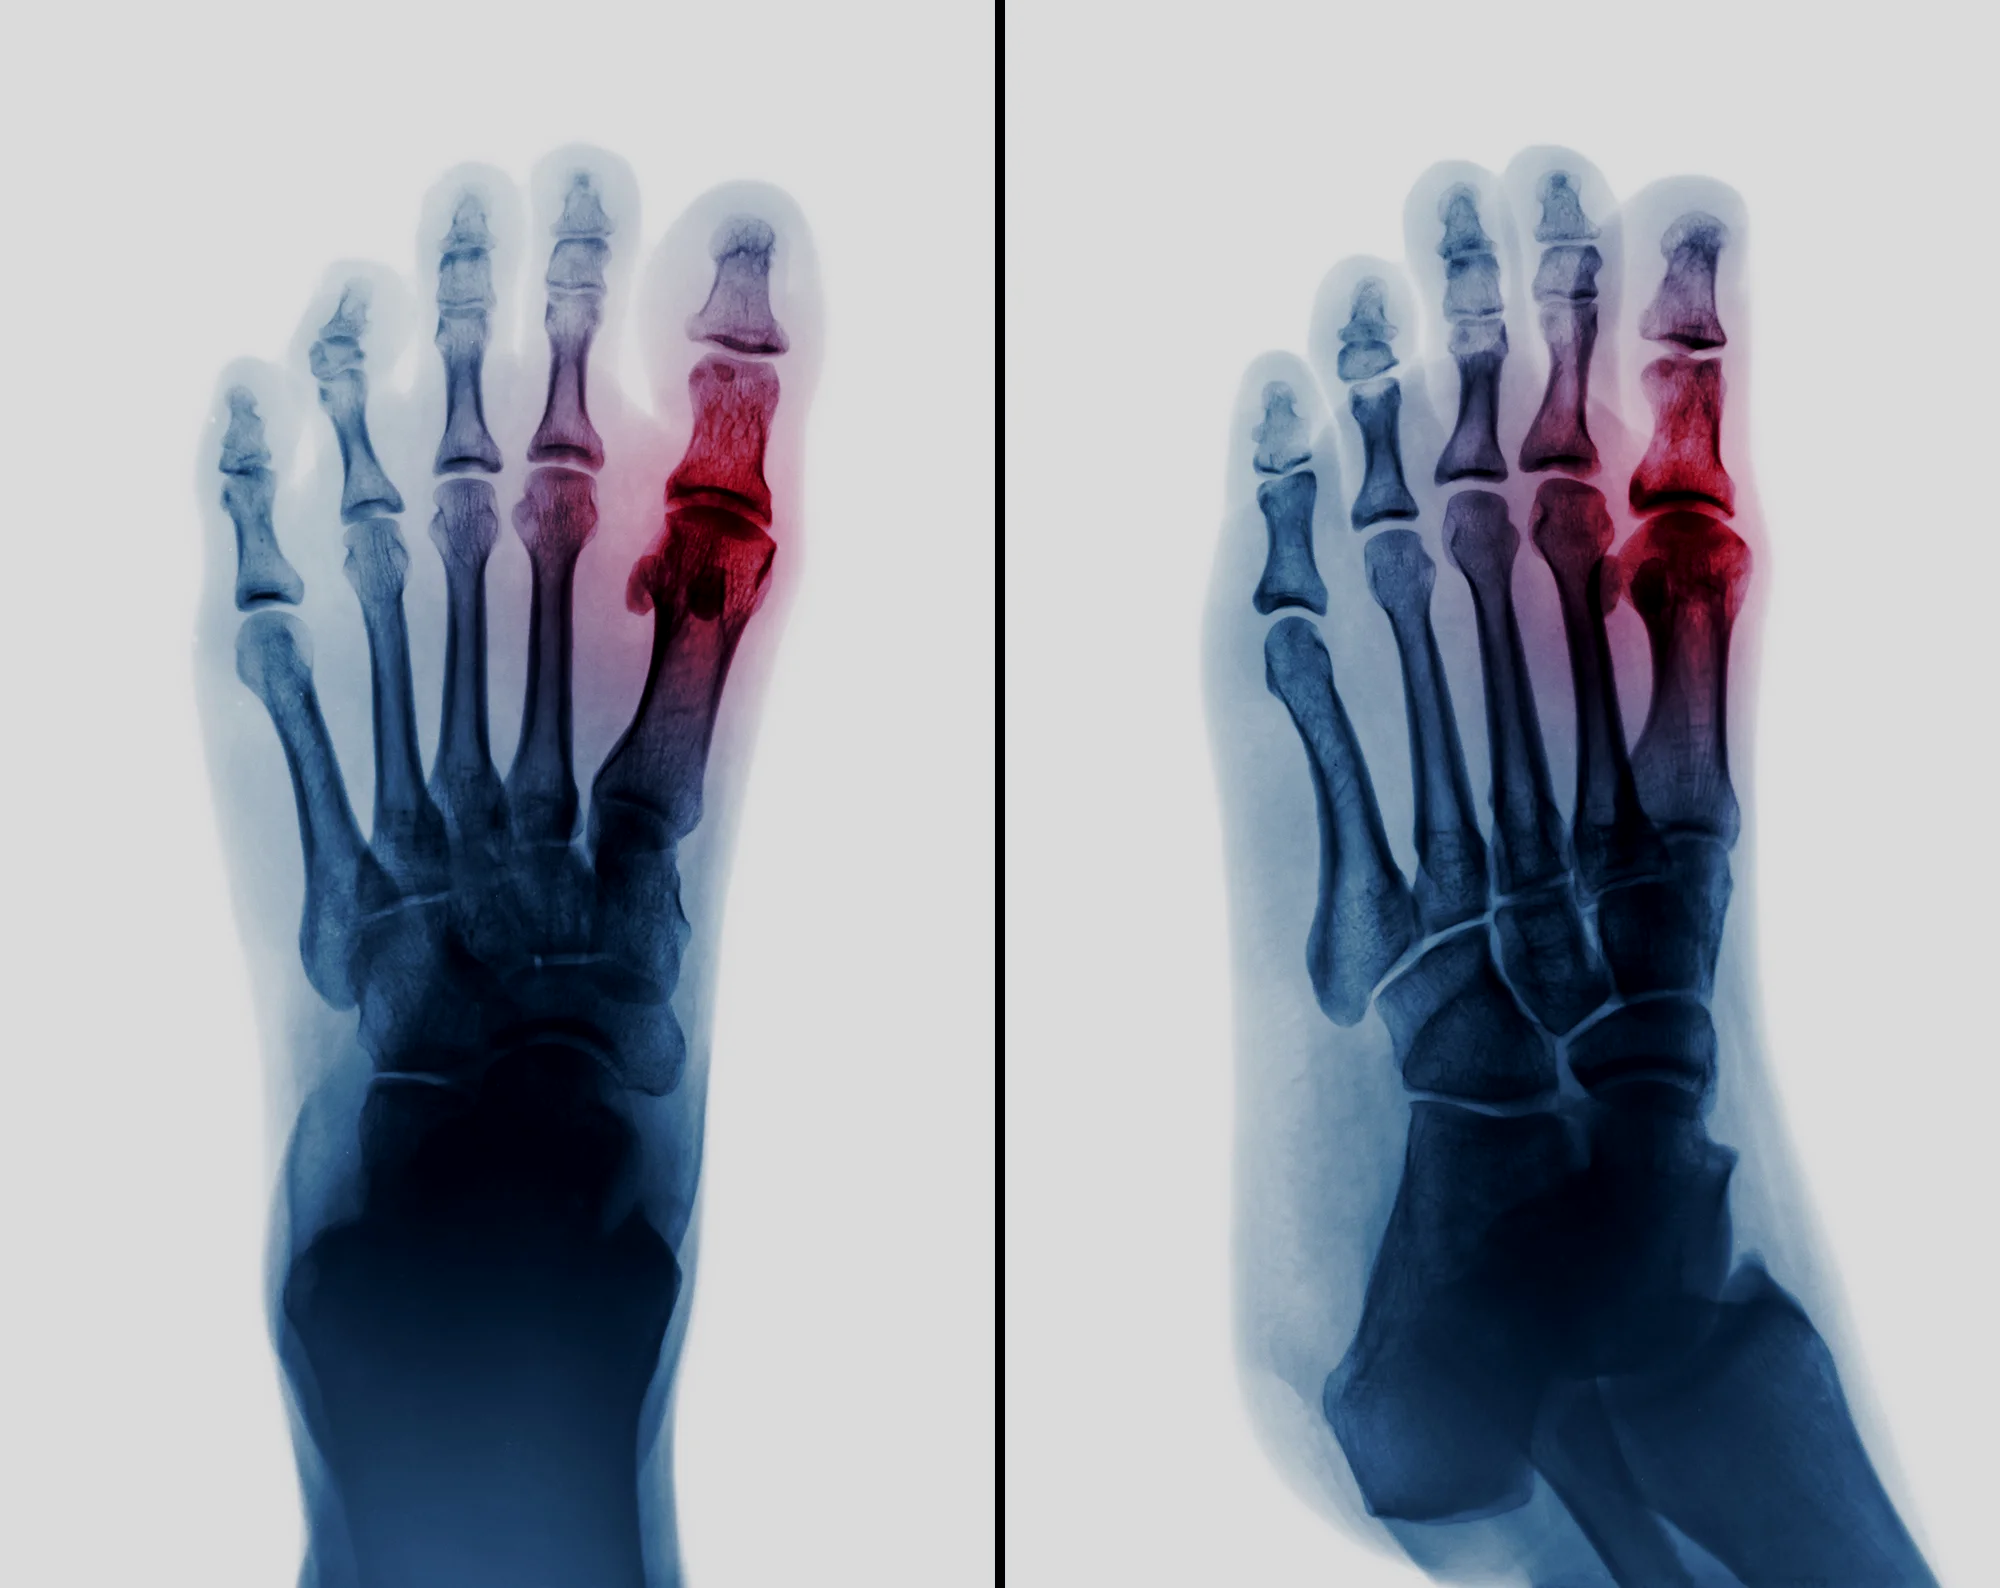

Metatarsalgia

You have got metatarsalgia which means pain in the ball of the foot. This may affect just one joint or several joints. Read more >>

Morton's Neuroma

A swelling around the nerve to two of your toes. Sometimes the swelling can cause the two affected toes to be pushed apart. Read more >>

Forefoot Reconstruction

Rheumatoid arthritis causes many or all of the toes to buckle and deform, making the joints in the forefoot prominent. Rubbing on the joints makes them red and painful. Read more >>